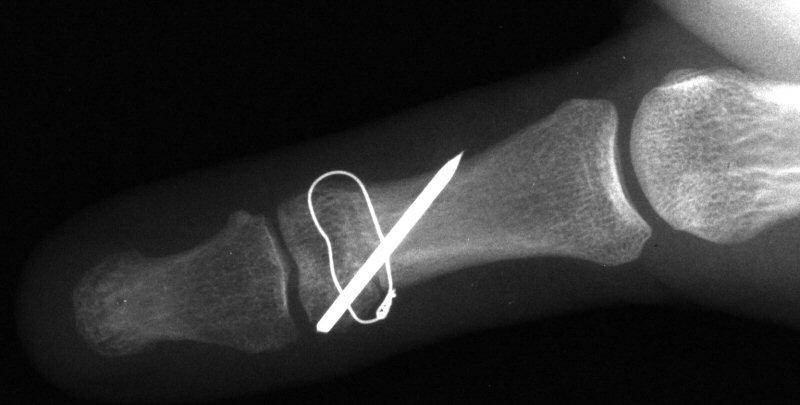

Intraosseous wire passed through pin tracts, interfragmentary pin:

Click for larger image